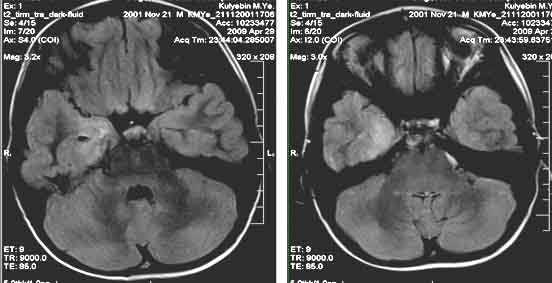

Туберозный склероз (синдром Бурневиля) встречается реже нейрофиброматоза. Его частота по данным литературы составляет около одного на 180 тыс. населения. От 20 до 40% случаев туберозного склероза унаследованы по аутосомно- доминантному типу, остальные возникли вследствии мутаций предположительно 9 и 11 пар хромосом (тип 1), либо 19 пары (тип 2). Поражение может затрагивать практически любые органы. Патогномоничными поражениями ЦНС являются корковые узлы в головном мозге и множественные субэпендимальные глиальные узлы , а также внутрижелудочковая гигантоклеточная астроцитома, встречаются сопутствующие аномалии - агенезия мозолистого тела, пахигирия, аневризмы. Характерны дерматологические проявления в виде множественных ангиофибром лица в форме «бабочки», бледные пятна на лице и груди, фибромы кожи, под ногтями и сетчатке глаза. Из других проявлений встречаются множественные ангиолипомы почек и печени, рабдомиомы сердца, лимфангиоматоз лёгких, костные склеротические и кистозные изменения. Диагноз туберозного склероза ставится при наличии у пациента 2 из перечисленных характерных признаков.

Корковые узлы - самое частое проявление туберозного склероза. Они расположены в коре головного мозга, деформируют её, захватывают прилегающее белое вещество и подвергаются кальцификации . При МРТ узлы изоинтенсивны серому веществу на Т1-взвешенных МРТ и чуть гиперинтенсивнее его на Т2-взвешенных. Контрастирование наблюдается в 5% случаев. В белом веществе обнаруживаются тяжи , отходящие радиально от желудочков. Корковые узлы и тяжи нередко называют «гамартомами», хотя они представляют собой скорее демиелинизацию и кальцификацию, чем истинную гетеротопию.

Туберозный склероз. Гамартомы. КТ, Т2-зависимая МРТ и FLAIR

Субэпендимальные, то есть проецирующиеся в желудочек, но растущие со стороны паренхимы мозга, узлы чаще расположены рядом с хвостатым ядром или гипоталамической бороздой сразу за отверстием Монро, реже в области III, IV желудочков и Сильвиева водопровода. На Т2-взвешенных томограммах субэпендимальные узлы умеренно гиперинтенсивны и часто содержат кальцинаты . От астроцитом их отличает не столь яркий сигнал и меньшие размеры. Контрастирование при введении препаратов гадолиния иногда наблюдается и в субэпендимальных узлах , и всегда в астроцитомах.

Туберозный склероз. Субэпендимальные узлы. Аксиальная Т-зависимая МРТ.